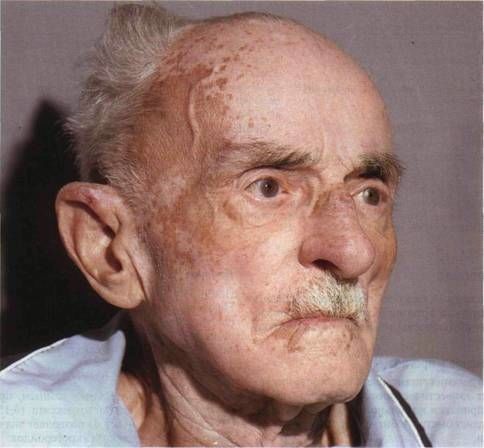

Визуальные материалы, связанные с болезнью Горхема-Стаута

Раздел: Альбом открытий